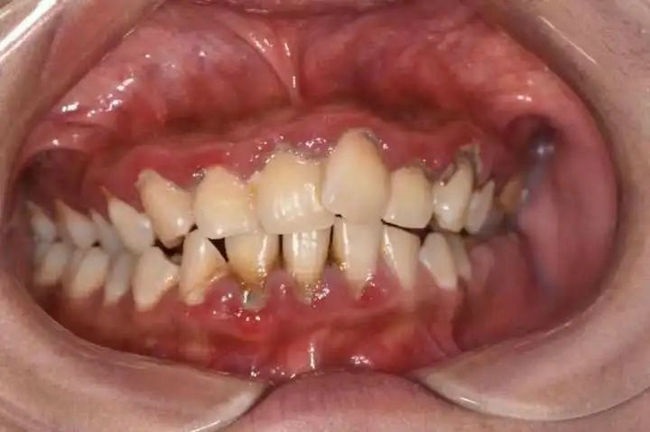

这是造成牙龈出血的主要原因。由于口腔卫生不佳,牙结石长期存在于牙缝、牙龈之间,牙龈受刺激出现炎症,表现为颜色暗红,形态肿胀,轻轻一碰就会出血,甚至出现自发出血。